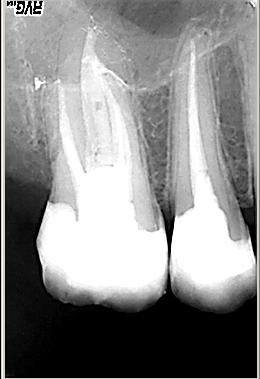

Distalexzentische Projektion

Distalexzentische Projektion mit zweitem Parodontalspalt in der mesiobuccalen Wurzel als deutlicher Hinweis für ein zusätzliches viertes Kanalsystem